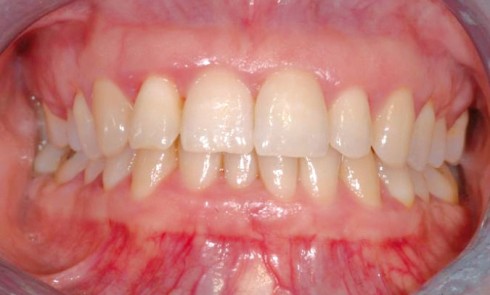

CFAO

Article réservé à nos abonnés CFAO : Nouvelles stratégies esthétiques assistées par ordinateur

La planification et la prévisibilité des résultats cliniques en réhabilitation esthétique représentent un véritable défi pour répondre aux besoins des...